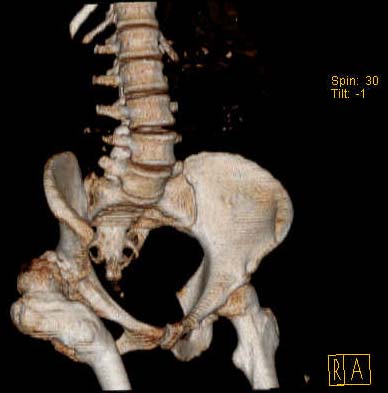

Уважаемые коллеги!Женщина, 35 летВ прошлом по поводу врожденного вывиха бедра перенесла операцию остеотомии по Шанцу

с удлинением правой ноги за счет бедра на уровне диафиза. В последнее время прогрессируют боли в правом тазобедренном суставе, порочное положение правой ноги, затруднена ходьба.Вопросы:1) Целесообразно ли эндопротезирование правого тазобедренного сустава?2) Целесообразный ли следующие действия: канал бедренной кости предполагаем вскрыть для введения ножки протеза на высоте угловой деформации, предполагаем низведение большого вертела с мышцами; протез будет подобран индивидуально, предполагается умеренная версия?В приложении рентгенограммы и трехмерная КТ.В цветном и более качественном варианте КТ размещена здесь

Наше общее мнение - проведение клиновидной остеотомии в зоне дополнительной точки опоры с ее иссечение и укорочением бедра, протезирование ножкой Вагнера.

Похожий случай представляем на ретгенограммах. Операция выполнена в 1996 г.